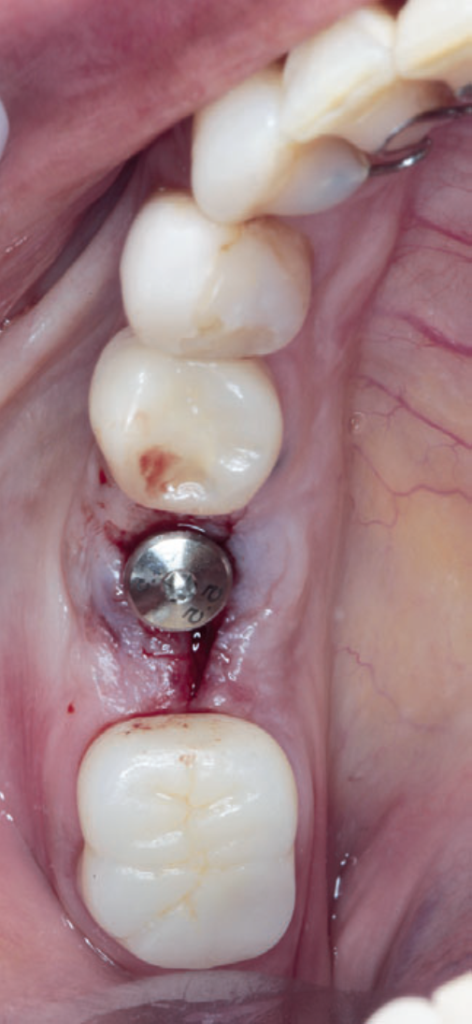

Para a instalação do implante imediato de corpo cônico cone-morse (Maestro, 4 mm x 9 mm, Implacil De Bortoli – São Paulo, Brasil), iniciou-se a fresagem de 9 mm com a fresa lança helicoidal 2.0, seguindo com a fresa cônica 3,5 mm x 9 mm com inclinação para mesial, na região mais centralizada entre a vestibular e a lingual do septo inter-radicular. Com o uso do Túnel Check Cônico 4.0 – instrumental que permite realizar a medição da profundidade da fresagem e sua inclinação –, verificou-se o paralelismo da perfuração para inserção do implante dentário (Figura 4). Em seguida, o implante dentário foi inserido com travamento final de 20 Ncm e recebeu o parafuso de cobertura correspondente (Figuras 5 e 6).

Para a regeneração óssea guiada, o substituto ósseo natural composto por hidroxiapatita bovina e colágeno do tipo I (Extra Graft XG-13) foi introduzido ao redor do implante para preenchimento do GAP (Figura 7). Depois, uma barreira regenerativa não absorvível (Cytoplast) foi recortada, adaptada e colocada, seguida por uma membrana biológica bovina (Figuras 8 e 9). O procedimento cirúrgico foi finalizado com a realização da sutura com fio de nylon 5.0. Para verificar o posicionamento do implante dentário, uma radiografia periapical foi realizada imediatamente à cirurgia (Figura 10).